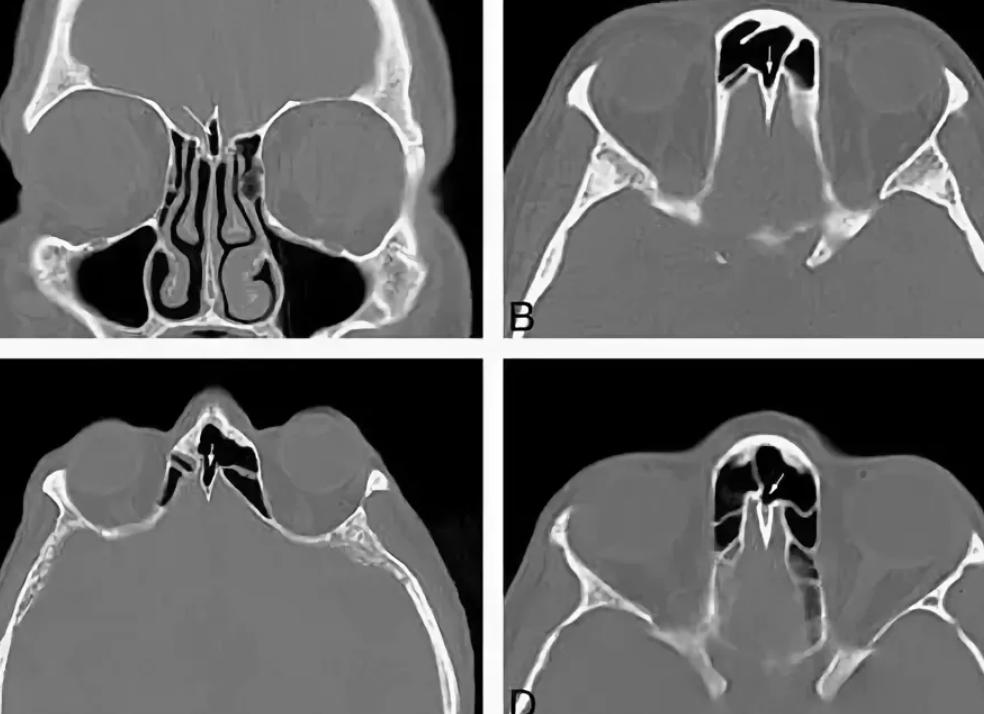

КТ органов грудной клетки называется исследование тканей и внутренних органов человека (в данном случае – области груди) посредством сканирования рентгеновским излучением. Благодаря своей высокой информативности, данный метод является очень востребованным при проведении диагностики болезней, способствуя выявлению с большой точностью аномалий, новообразований, травматических последствий и других нарушений в грудине, легких, пищеводе, дыхательных путях, кровеносных сосудах, плевре, молочных железах, лимфатических узлах, ребрах. Помимо этого, КТ оценивает месторасположение, структуру данных органов, в прямом смысле слова проливая свет на любую патологию тканей и органов, – даже на ранней стадии и протекающую в скрытой форме. Подробнее ...